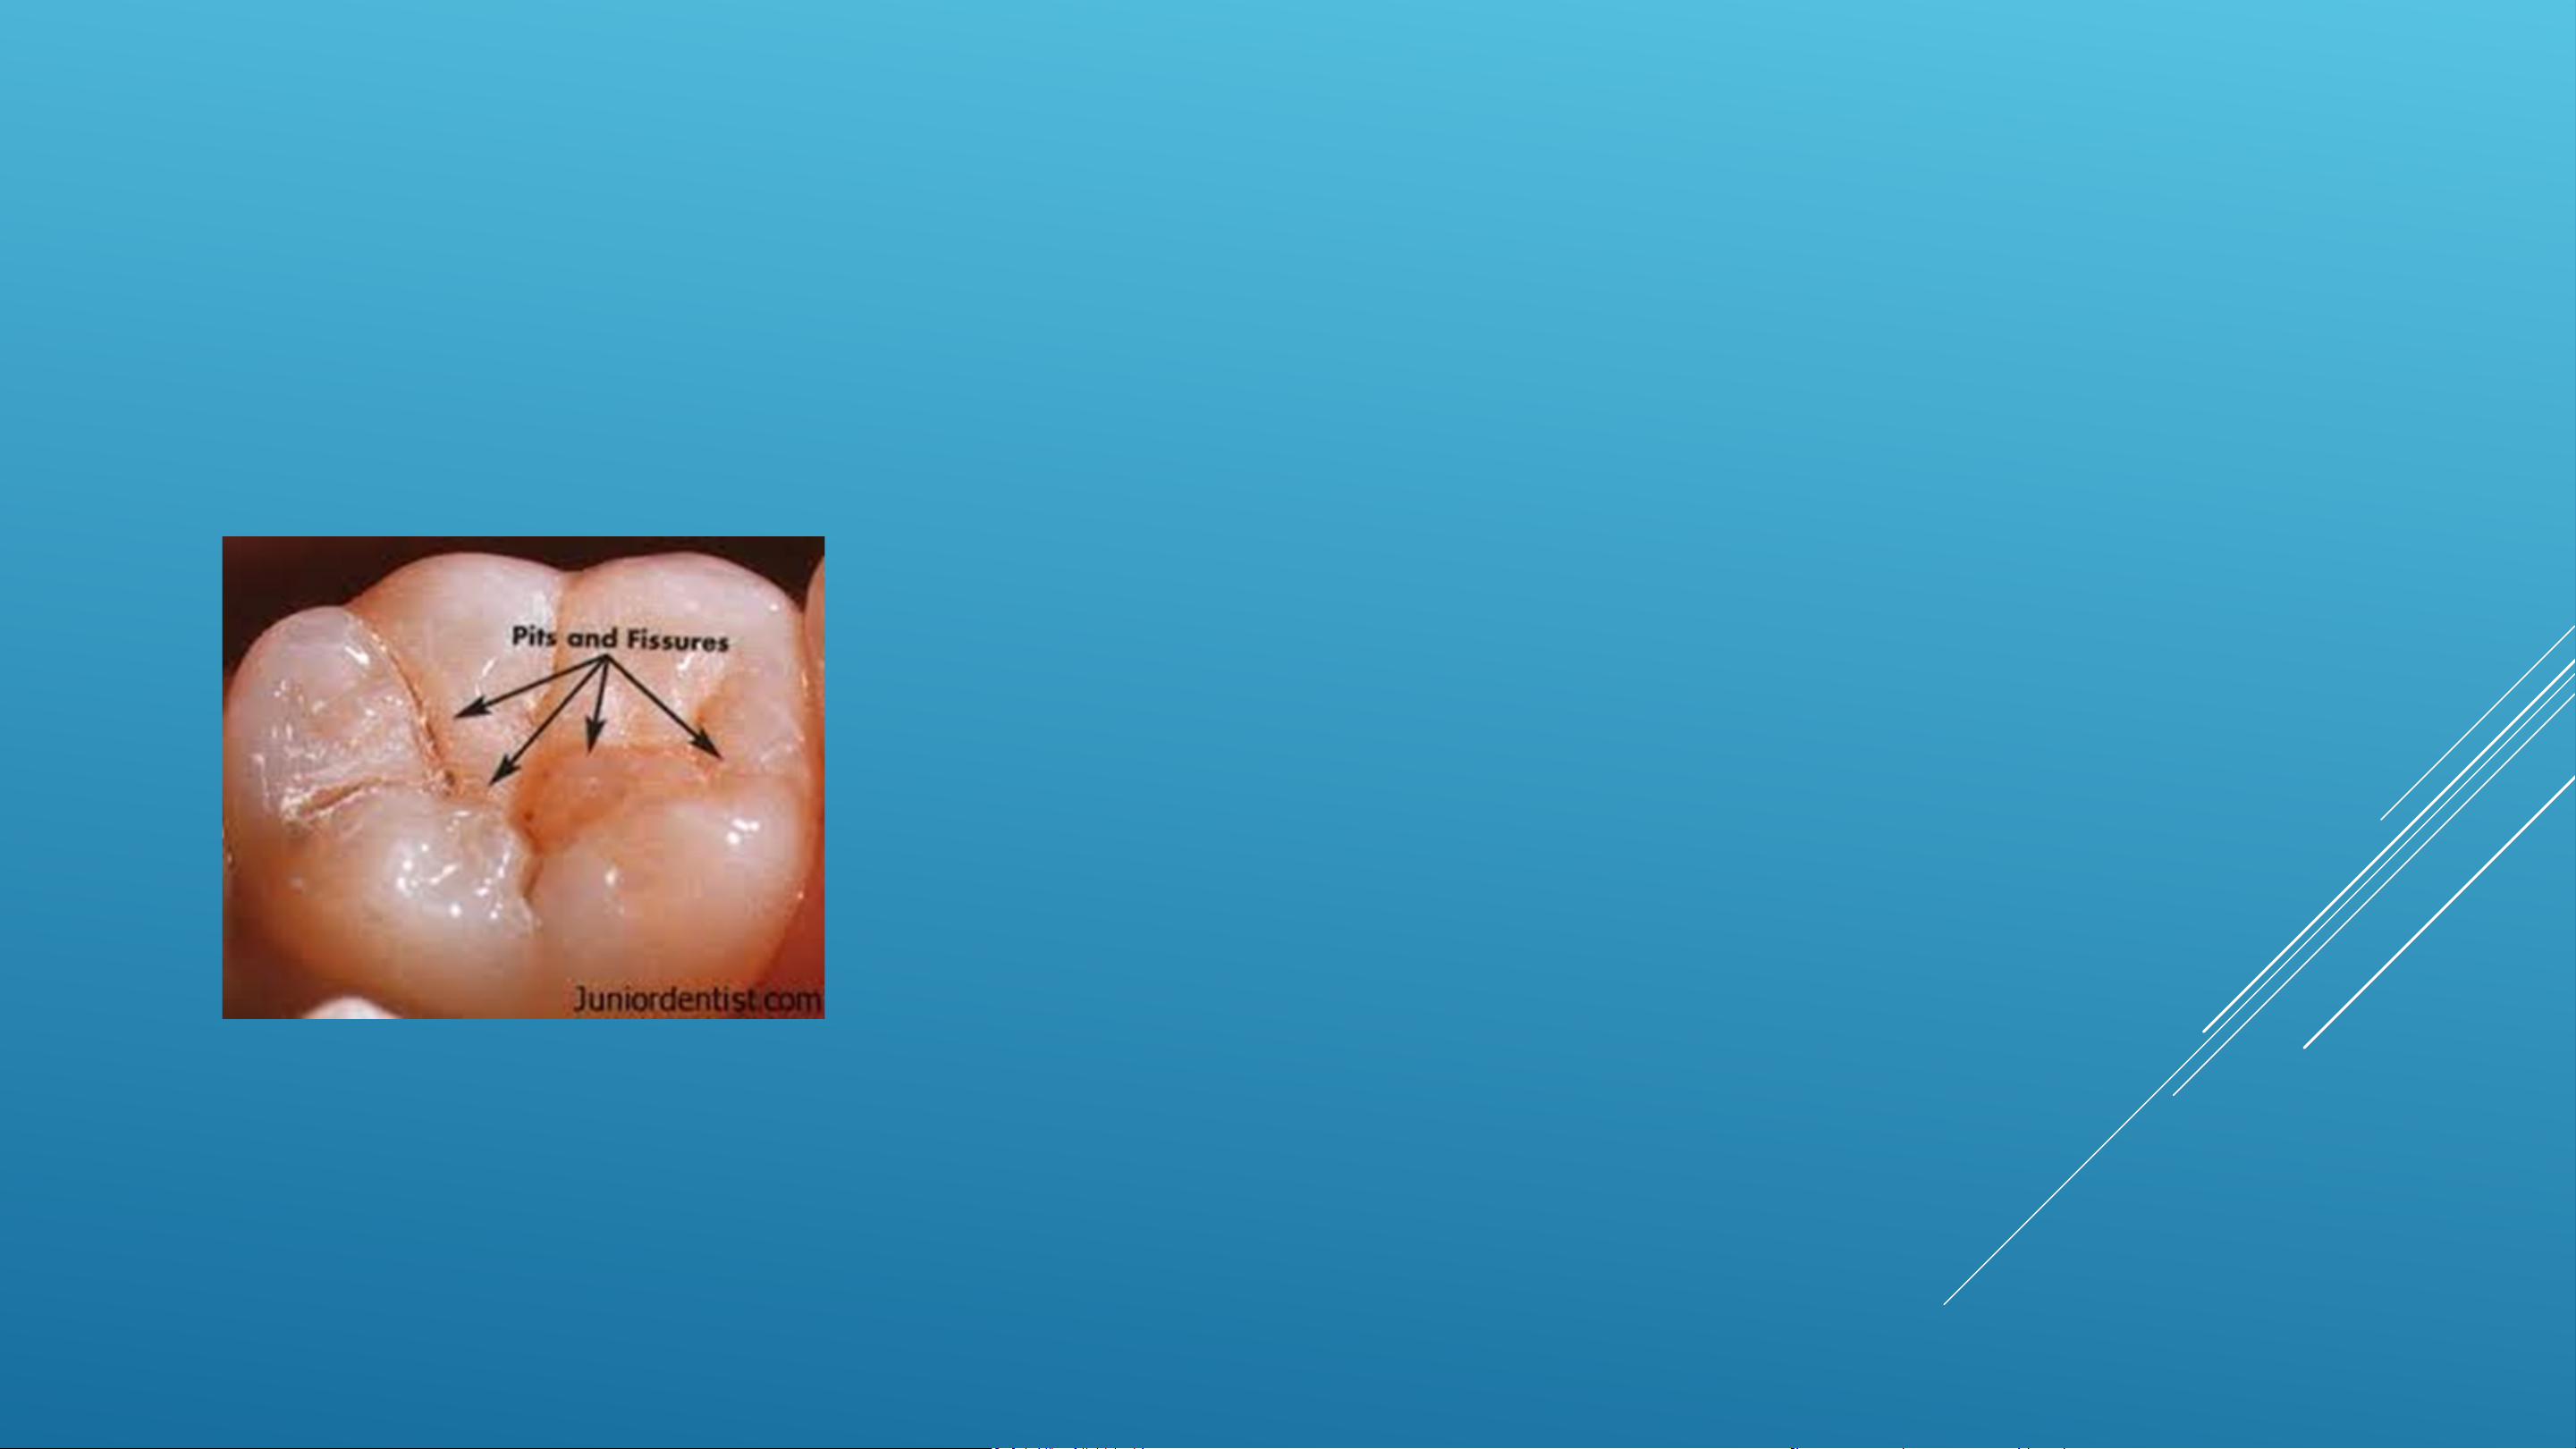

Sâu răng phần lớn là có thể phòng

ngừa được, nhưng vẫn là một vấn

đề hết sức nghiêm trọng. Các phát

hiện từ cuộc khảo sát dịch tễ học

nha khoa quốc gia ở Anh năm

2015 ở trẻ 5 tuổi của Cơ quan Y tế

Công cộng Anh (PHE) đã chỉ ra

rằng năm 2015 ở Anh có đến 1/4

(tức 25%) số trẻ em 5 tuổi bị sâu

răng, với trung bình 3-4 chiếc răng

bị ảnh hưởng. Phần lớn các trường

hợp bị sâu răng đều không được điều trị.